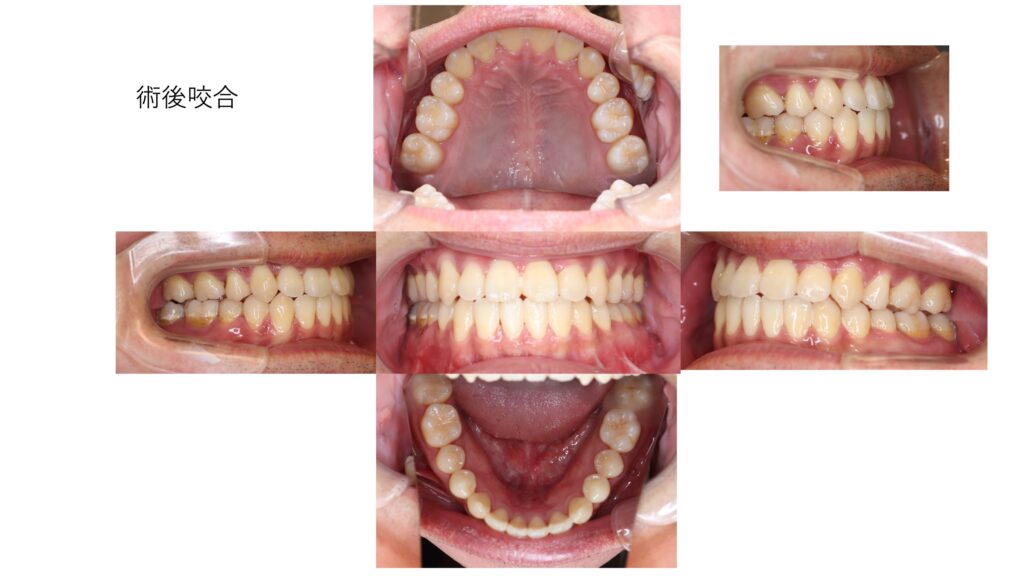

反対咬合は消失していて、咬合は安定しています。レントゲンでは後戻りを認めません。